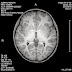

The MRI Scan revealed that Reagan had multiple pineal cysts which altogether amassed 1 cm large in size. These cysts are fluid-filled sacks located on the Pineal Gland (often referred to as 'the third eye') in the very center of the brain at the end of the brain stem and next to the pituitary gland. On the MRI scan photograph to the right, the cyst looks like a porous ball. The Pineal Gland itself is not very well researched, although it is one of three glands that comprise the Endocrine System in the brain. Its function is often referred to as insignificant. What they know about its function is that it is responsible for producing melatonin, something children produce an abundance of naturally that enables them to sleep more than adults do. As you grow older, the Pineal Gland produces less melatonin. The only form of treatment available for a growing, symptomatic Pineal Cyst or Tumor is surgical resection. But because of its location, it is the most difficult surgery to perform. In most cases pineal cysts are benign. Neurosurgeons will only remove the cyst if it's symptomatic and growing. Most 'neuro' doctors refer to this cyst as an 'incidental finding.' They will likely tell their patients that 'it is not causing their migraines,' or my favorite, 'It is not causing the autism,' and that they have nothing to worry about. But a symptomatic Pineal Cyst is something that warrants monitoring, concern, and credit for causing a myriad of problems - it is not something to disregard or take lightly. This blogger writes about his Pineal Cyst and his wishes to have it removed, and provides great visuals that show exactly where the cyst lies in the brain.